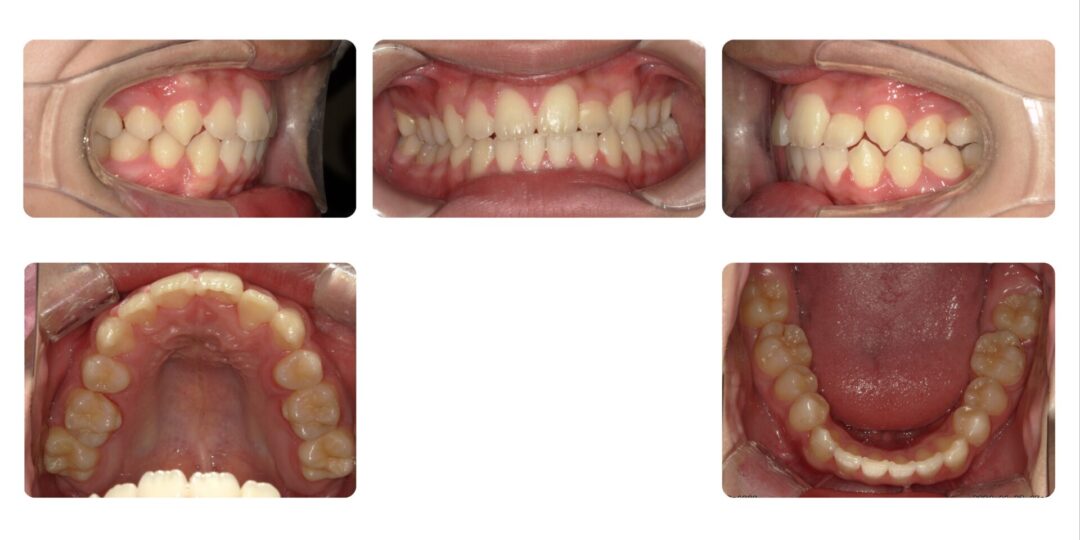

第二期矯正治療後